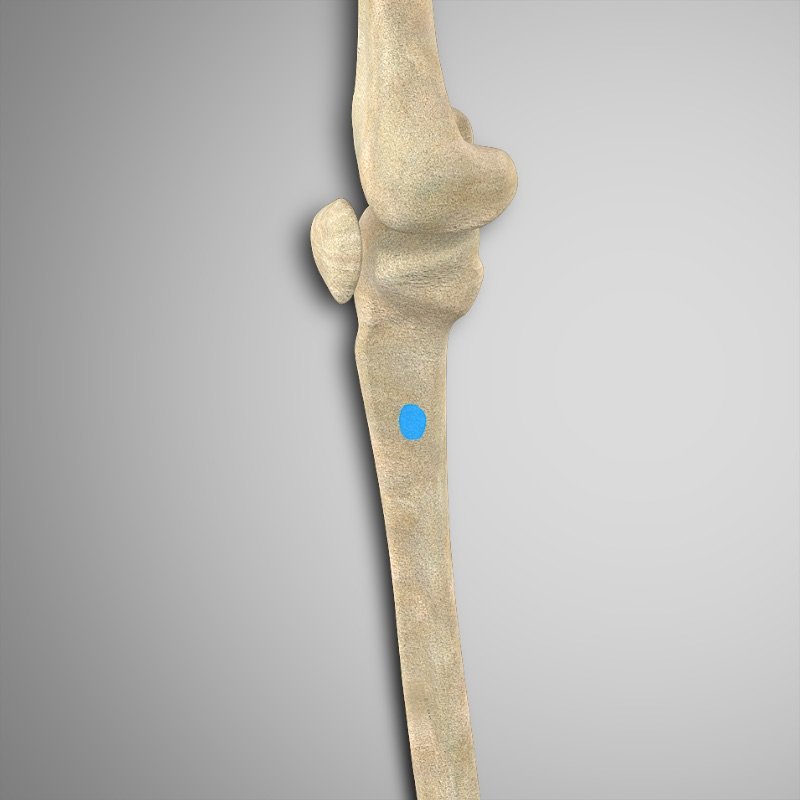

- Bíceps femoral (ambas cabezas) – Cabeza del peroné

- Semimembranoso – Cóndilo tibial medial posterior

- Semitendinoso – Tendón anserino.